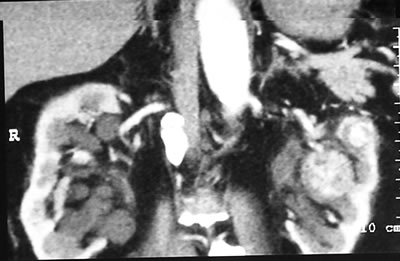

Спиральная

компьютерная томография (СКТ)

Правая почка: в передней

губе в среднем сегменте образование 37*35*23 мм, множественные

кисты диаметром до 20 мм и киста в верхнем сегменте

– 45*36*35 мм.

Левая почка: два образования 15 мм в верхнем

сегменте и 40 мм в среднем сегменте.

Фиброзная касула, регионарные л/у – интактны.